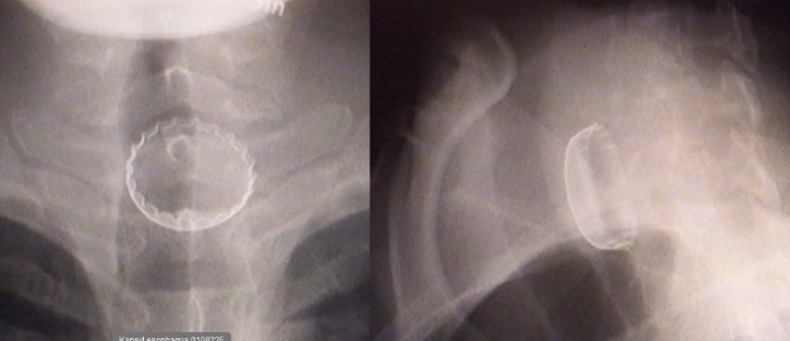

Kapsyl

Kan denna personen andas tror du?

A

Kan inte komma ner i trakea (förmodligen kan de andas ju)